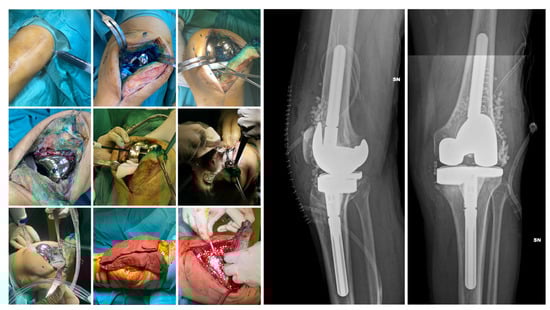

Surgical Technique. The choice of surgical procedure (DAPRI, 1-stage, 1.5-stage, or 2-stage revision) needed was based on patient-specific factors, time since the onset of symptoms and previous surgery, and the identification of an etiological agent. The DAPRI surgical procedure was performed according to the technique described by Indelli et al. [33] for the knee and adapted to the joint in question. The original technique involves the injection of a methylene blue solution into the joint to highlight contaminated areas, followed by aggressive debridement and a combined thermal (argon plasma coagulator, APC) and mechanical (brush impregnated with 4% chlorhexidine gluconate) removal of biofilm from the metallic surfaces, along with the replacement of all mobile components of the prosthesis (Figure 2).

Figure 2.

DAPRI procedure for the knee. Methylene blue solution is injected into the joint before skin incision is made and distributed with flexion–extension cycles. The polyethylene insert is removed, and a tumor-like debridement of the stained portions is performed. Thermal debridement of the prosthetic surfaces is performed with an APC, followed by mechanical debridement with a sponge soaked in 4% chlorhexidine gluconate and irrigation with normal saline and povidone–iodine solution. Finally, the insert is replaced, and calcium sulfate beads loaded with the targeted antibiotic(s) are positioned. In the postoperative X-rays the beads are visible.